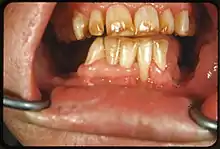

It appears as a range of visual changes in enamel[4] causing degrees of intrinsic tooth discoloration, and, in some cases, physical damage to the teeth. The severity of the condition is dependent on the dose, duration, and age of the individual during the exposure.[1] The "very mild" (and most common) form of fluorosis, is characterized by small, opaque, "paper white" areas scattered irregularly over the tooth, covering less than 25% of the tooth surface. In the "mild" form of the disease, these mottled patches can involve up to half of the surface area of the teeth. When fluorosis is moderate, all of the surfaces of the teeth are mottled and teeth may be ground down and brown stains frequently "disfigure" the teeth. Severe fluorosis is characterized by brown discoloration and discrete or confluent pitting; brown stains are widespread and teeth often present a corroded-looking appearance.[1]

The adequate diagnosis of fluorosis can be diagnosed by visual clinical examination. This requires inspection of dry and clean tooth surfaces under a good lighting.[6] There are individual variations in clinical fluorosis manifestation which are highly dependent on the duration, timing, and dosage of fluoride exposure.There are different classifications to diagnose the severity based on the appearances. The clinical manifestation of mild dental fluorosis is mostly characterised a snow flaking appearance that lack a clear border, opaque, white spots, narrow white lines following the perikymata or patches as the opacities may coalesce with an intact, hard and smooth enamel surface on most of the teeth.[7] With increasing severity, the subsurface enamel, all along the tooth becomes more porous. Enamel may appear yellow/ brown discolouration and/ or many and pitted white-brown lesions that look like cavities. They are often described as "mottled teeth".[8] Fluorosis does not cause discolouration to the enamel directly, as upon eruption into the mouth, affected permanent teeth are not discoloured yet. In dental enamel, fluorosis causes subsurface porosity or hypomineralizations, which extend toward the dentinal-enamel junction as the condition progresses and the affected teeth become more susceptible to staining. Due to diffusion of exogenous ions (e.g., iron and copper), stains develop into the increasingly and abnormally porous enamel.[7]

| Moderate | 4 | All enamel surfaces of the teeth are affected and surfaces subject to attrition show wear. Brown stain is frequently a disfiguring feature |

| Severe | 5 | All enamel surfaces are affected and hypoplasia is so marked that the general form of the tooth may be affected. The major diagnostic sign of this classification is discrete or confluent pitting. Brown stains are widespread and teeth often present a corroded-like appearance. |